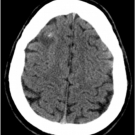

A 56-year-old woman presented to the emergency room due to an alteration in mental status. The family reported that in recent weeks she became distracted, lethargic, and drowsy at times with reduced...